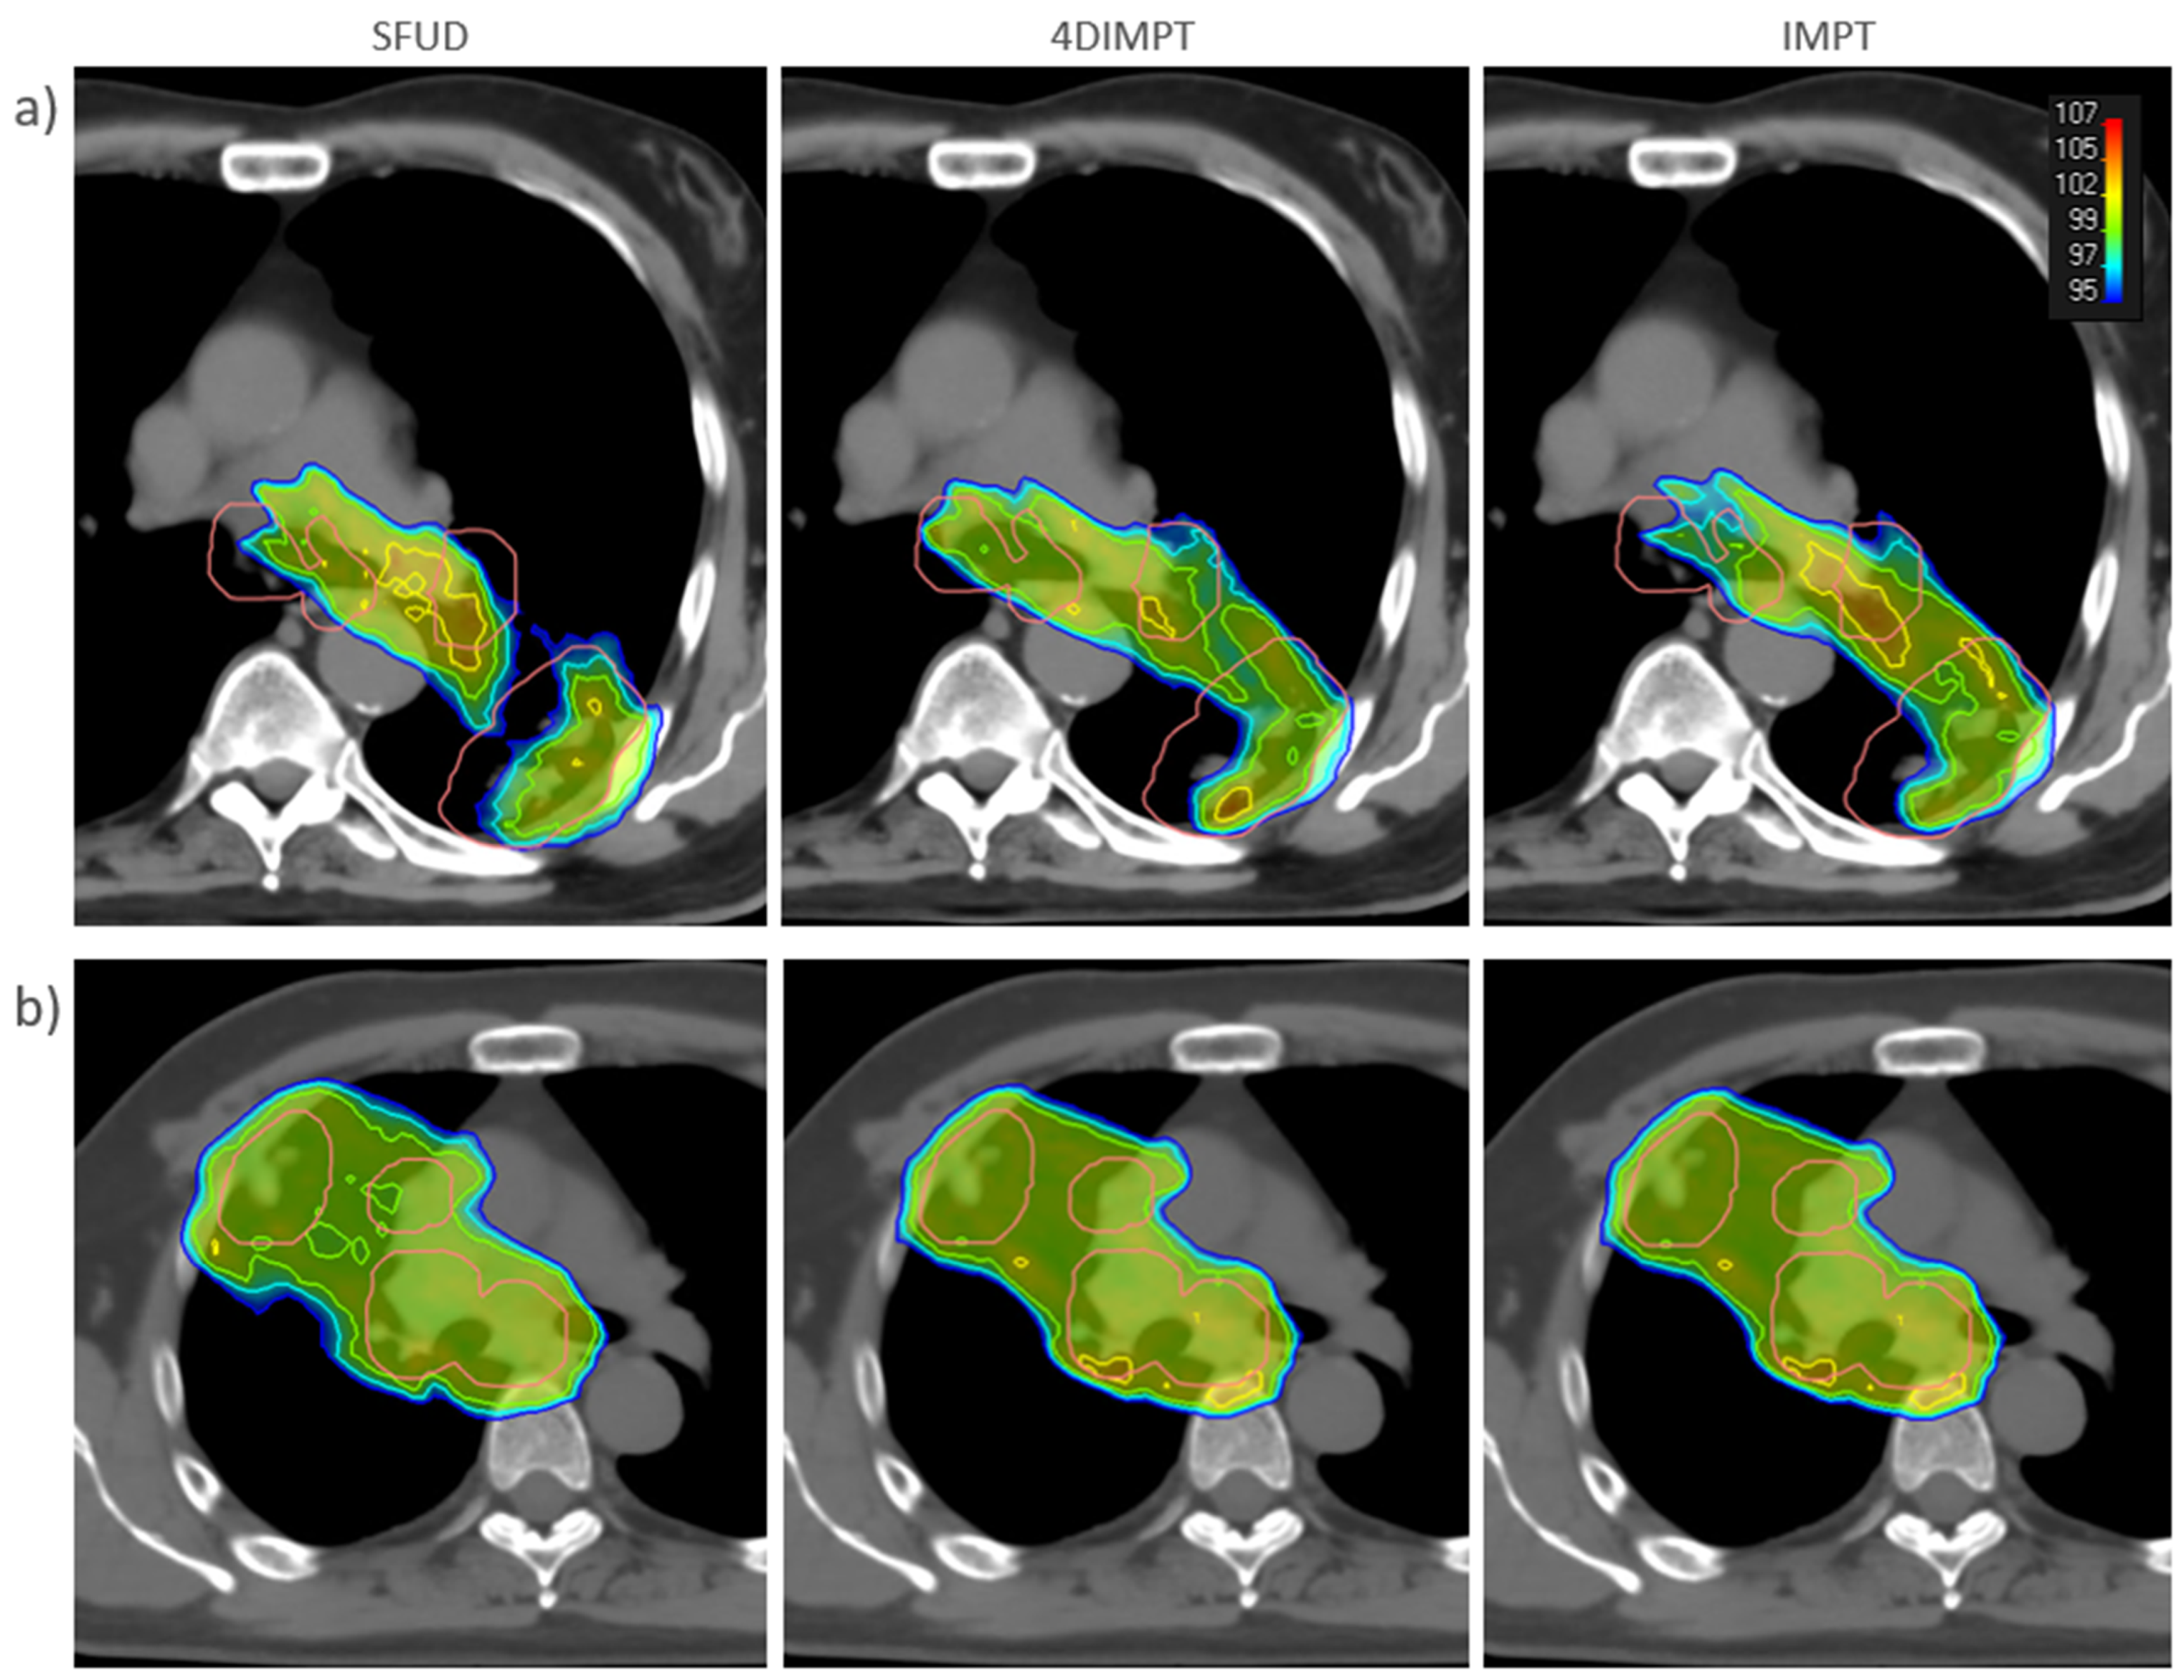

3.2. Target Coverage and OAR Sparing at Plan

3.3. Target Dose Robustness at Plan and Start

3.4. OAR Dose Robustness at Plan and Start

3.5. Target Coverage and OAR Sparing at Start